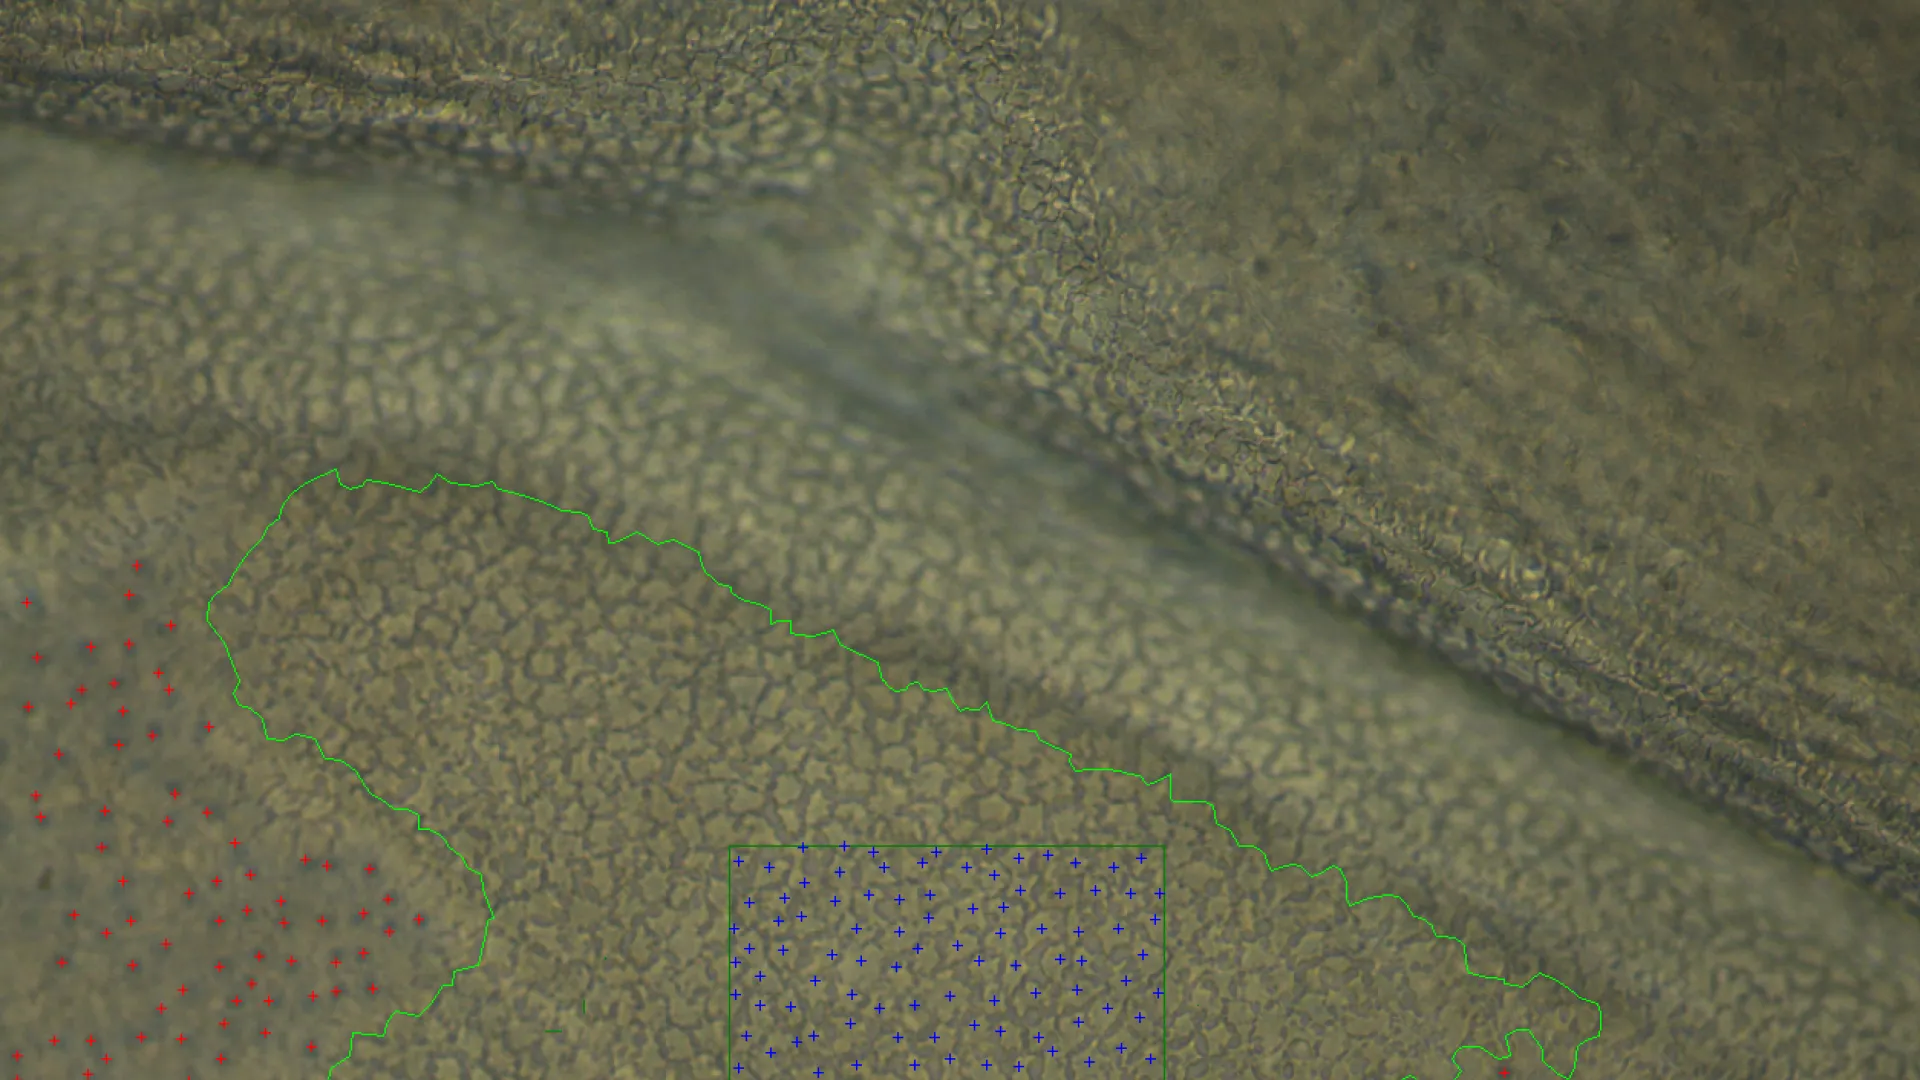

KerifAI utilise la vision par ordinateur et le deep learning pour identifier, compter, segmenter

et classifier les cellules endothéliales sur une surface représentative des tissus, améliorant

précision, reproductibilité et fiabilité. Les techniciens annotent les images de cornées pour

entraîner les algorithmes, qui permettent désormais de qualifier des tissus auparavant écartés